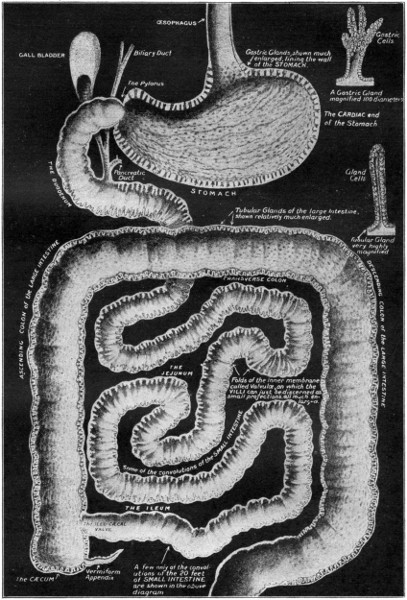

ITS STRUCTURE—ORGANIZATION INTO SYSTEMS—FUNCTIONS—SPECIAL SENSES—NERVOUS SYSTEM—PERSONAL HYGIENE—PREVENTION OF DISEASE—INTERDEPENDENCE OF BODY AND MIND—EUGENICS—ILLUSTRATIONS AND CHARTS.